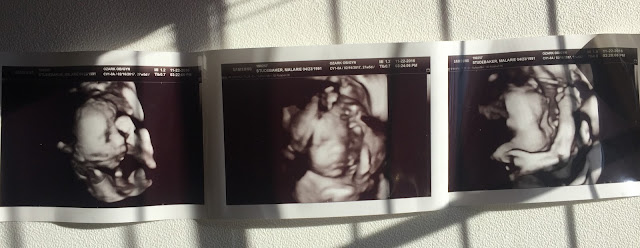

During the ultrasound we had some pretty adorable photos of Sawyer, except the umbilical cord was right in front of his face the whole time. That didn't stop us from seeing his adorable little nose though! It is crazy how one tiny little feature can make your heart melt. The doctor told me he is still measuring in the 40th percentile and is weighing 4 pounds. If he keeps this steady growth he should be an 8 pound baby when he arrives. Hopefully he doesn't hit a huge growth spurt while he is still cooking.